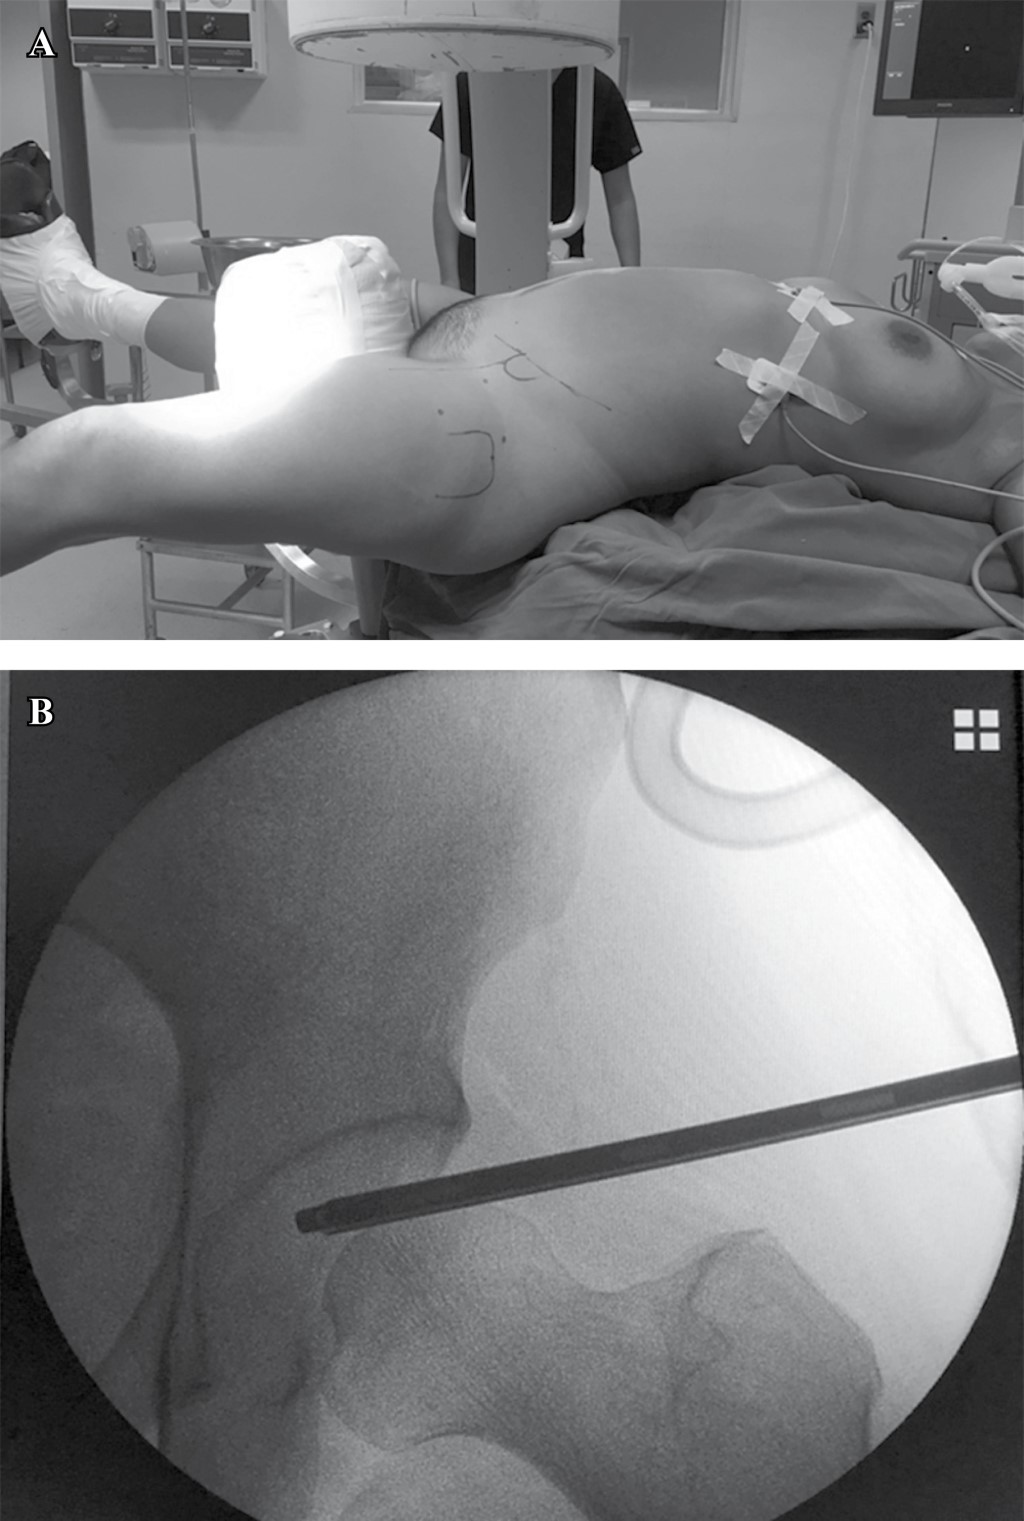

La paciente fue hospitalizada y programada para su manejo quirúrgico definitivo. Se realizó planificación en modelo plástico (Figura 2) y se decidió realizar reducción cerrada y fijación interna bajo principio biomecánico de compresión interfragmentaria31 y asistir reducción bajo visión directa mediante artroscopía de cadera.

Técnica quirúrgica: bajo anestesia general controlada, se posicionó a la paciente en decúbito supino sobre mesa quirúrgica de reducción de fracturas con la extremidad pélvica en tracción, utilizando fluoroscopio para visualizar la articulación coxofemoral (Figura 3).

Figura 2

Figura 3